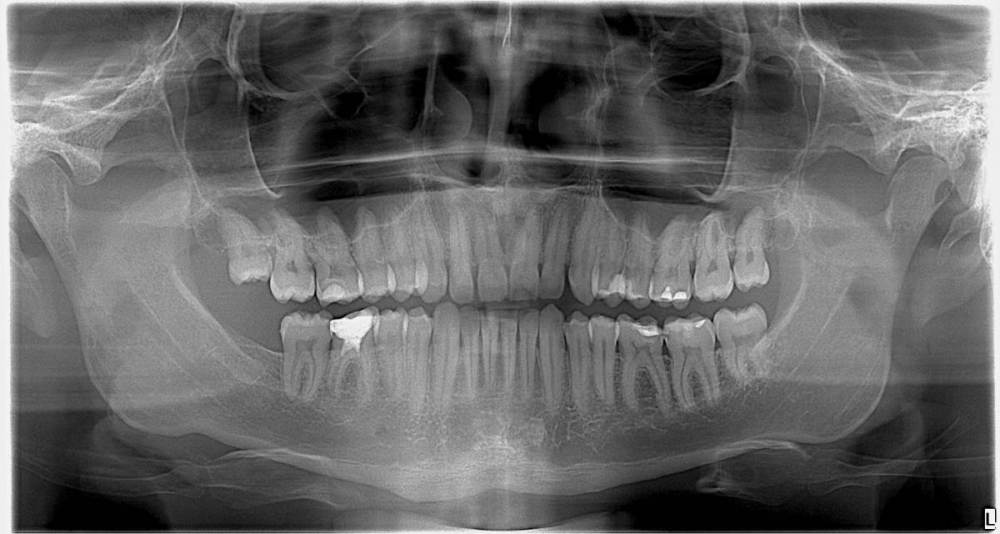

Stomach Опубликовано 11 марта, 2024 Поделиться Опубликовано 11 марта, 2024 Добрый день. 1. Над рогом пульпы 36 зуба тонкая белая полоса - это артефакт или образование вторичного (заместительного) дентина в связи с прогрессированием вторичного кариеса? 2. Есть ли где-то, исходя из представленной ОПТГ, кариозные полости? Благодарю Ссылка на комментарий

red_butler Опубликовано 11 марта, 2024 Поделиться Опубликовано 11 марта, 2024 4 минуты назад, Stomach сказал: . Над рогом пульпы 36 зуба тонкая белая полоса - это артефакт или образование вторичного (заместительного) дентина в связи с прогрессированием вторичного кариеса? артефакт 5 минут назад, Stomach сказал: Есть ли где-то, исходя из представленной ОПТГ, кариозные полости? 3.6 3.7 4.6 периодонтит 1 Ссылка на комментарий

Stomach Опубликовано 11 марта, 2024 Автор Поделиться Опубликовано 11 марта, 2024 55 минут назад, red_butler сказал: артефакт 3.6 3.7 4.6 периодонтит Благодарю за оперативный ответ! А под пломбой зуба 26 тёмная полоса - не начало вторичного кариеса? Ссылка на комментарий

red_butler Опубликовано 11 марта, 2024 Поделиться Опубликовано 11 марта, 2024 9 минут назад, Stomach сказал: Благодарю за оперативный ответ! А под пломбой зуба 26 тёмная полоса - не начало вторичного кариеса? нет 1 Ссылка на комментарий

Stomach Опубликовано 13 марта, 2024 Автор Поделиться Опубликовано 13 марта, 2024 (изменено) 11.03.2024 в 18:09, red_butler сказал: артефакт 3.6 3.7 4.6 периодонтит Благодарю. А в 36 пломбу новую поставить просто или уже ВКЛАДКУ целесообразнее, считаете? Изменено 13 марта, 2024 пользователем Stomach Ссылка на комментарий

red_butler Опубликовано 14 марта, 2024 Поделиться Опубликовано 14 марта, 2024 18 часов назад, Stomach сказал: Благодарю. А в 36 пломбу новую поставить просто или уже ВКЛАДКУ целесообразнее, считаете? коронку Ссылка на комментарий